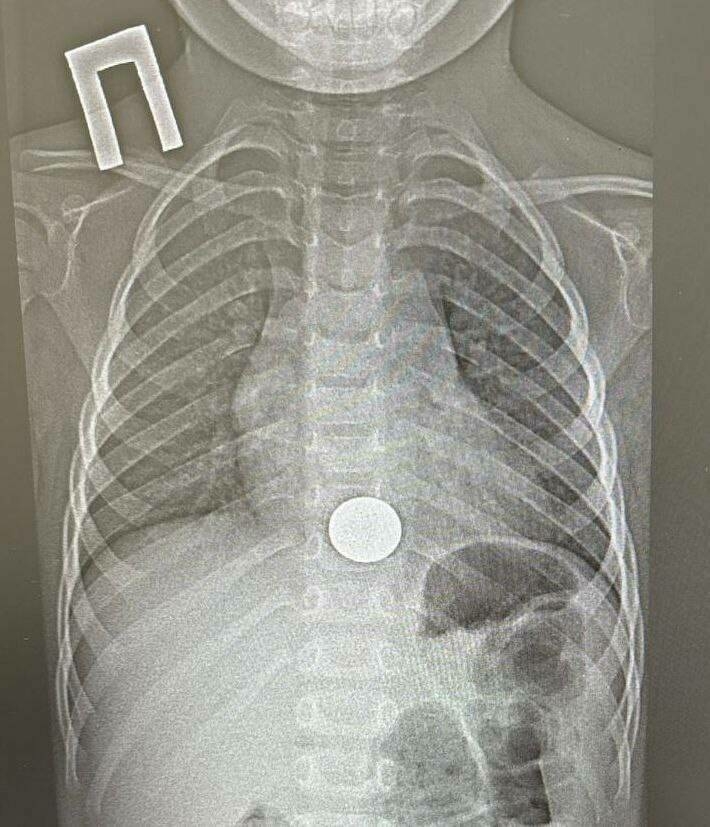

Түбән Камада табиблар тимер тәңгә йоткан баланы коткарган

Түбән Кама район балалар хастаханәсе табиблары баланың үңәченнән тимер тәңкә чыгарган. Бу хакта медицина учреждениесенең телеграм-каналында хәбәр иттеләр.

Бу хәл 15 декабрьдә булган. Хастаханәгә өч яшьлек баланы алып килгәннәр. Малайның әти-әнисе хәбәр иткәнчә, бала күкрәк читлеге эчендә авыртуга зарланган. Ачыкланганча, малай ялгыш тимер тәңкә йоткан булган. Ул бу хакта шунда ук әти-әнисенә әйткән.

Баланы оператив рәвештә Түбән Кама перинаталь үзәкле район балалар хастаханәсенә алып килгәннәр. Балалар хирургы, врач-эндоскопист Игорь Шогоров эндоскоп ярдәмендә чит әйберне алган. Манипуляция бер минут чамасы дәвам иткән. Процедурадан соң баланы күзәтү өчен хирургия бүлегенә күчергәннәр, ә икенче көнне өйгә кайтарып җибәргәннәр.

Табиблар сөйләгәнчә, гаилә вакытында ярдәм сорап мөрәҗәгать итү сәбәпле, баланы җитди нәтиҗәләрдән саклап кала алганнар. Тәңкә үңәчтә озаграк булган очракта чит әйбер органны имгәтергә һәм куркыныч нәтиҗәләргә китерергә мөмкин иде, дип билгеләп үткән белгечләр.